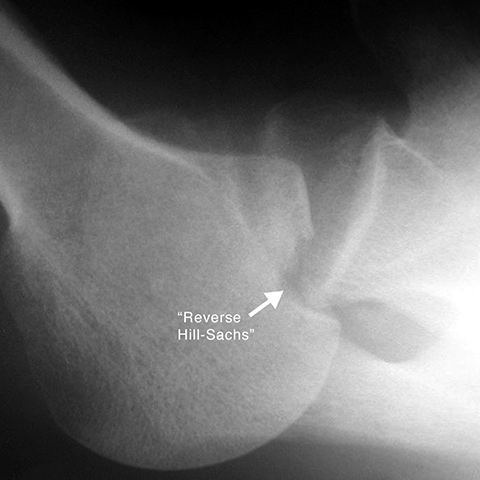

Reverse Hill-Sachs fracture